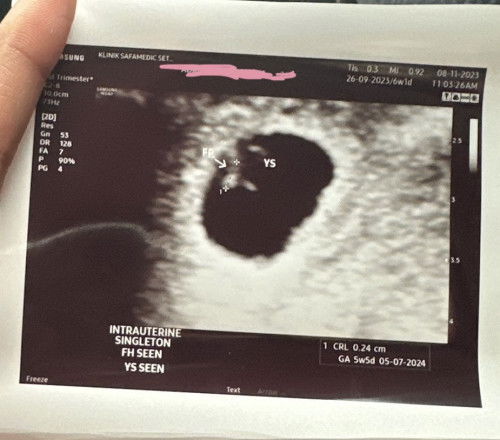

Minta pendapat dan pengalaman semua, sy last period pada 27/9 saya kira patutnya kandungan dah 6 weeks. Tp saya pergi scan sbb kdg2 perut cramp dan sakit pinggang, tp result scan 5 weeks and 6 days normal ke dia mcm x telly? And kalau ikut pandangan mata semua, ada kah shape kantung ni perfectly bulat? Atau ada tanda2 irregular shape? Tp td scan alhamdulillah dah nampak kantung, yolk sac dan heartbeat.. boleh bg pendapat tak mommies smua? 😄